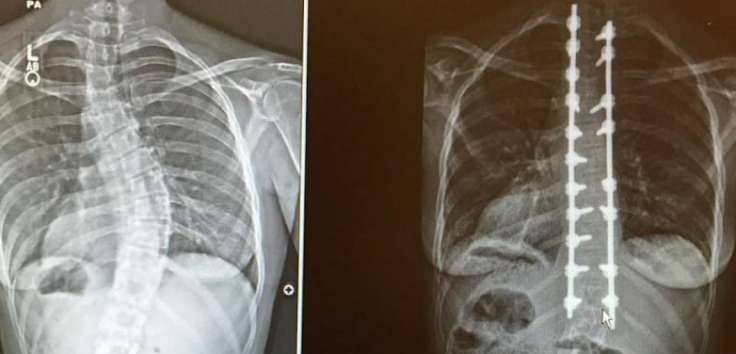

▼托马斯医生检查后,认为她的问题很严重。多年来,她的脊柱已经侧弯45度,想要治疗必须做手术。但手术也有风险,所以要如何抉择,还需要卡洛琳自己做决定。

▼手术3个月后,卡洛琳重新开始工作,她的模特儿事业进展顺利,生活中的不便也消失了。